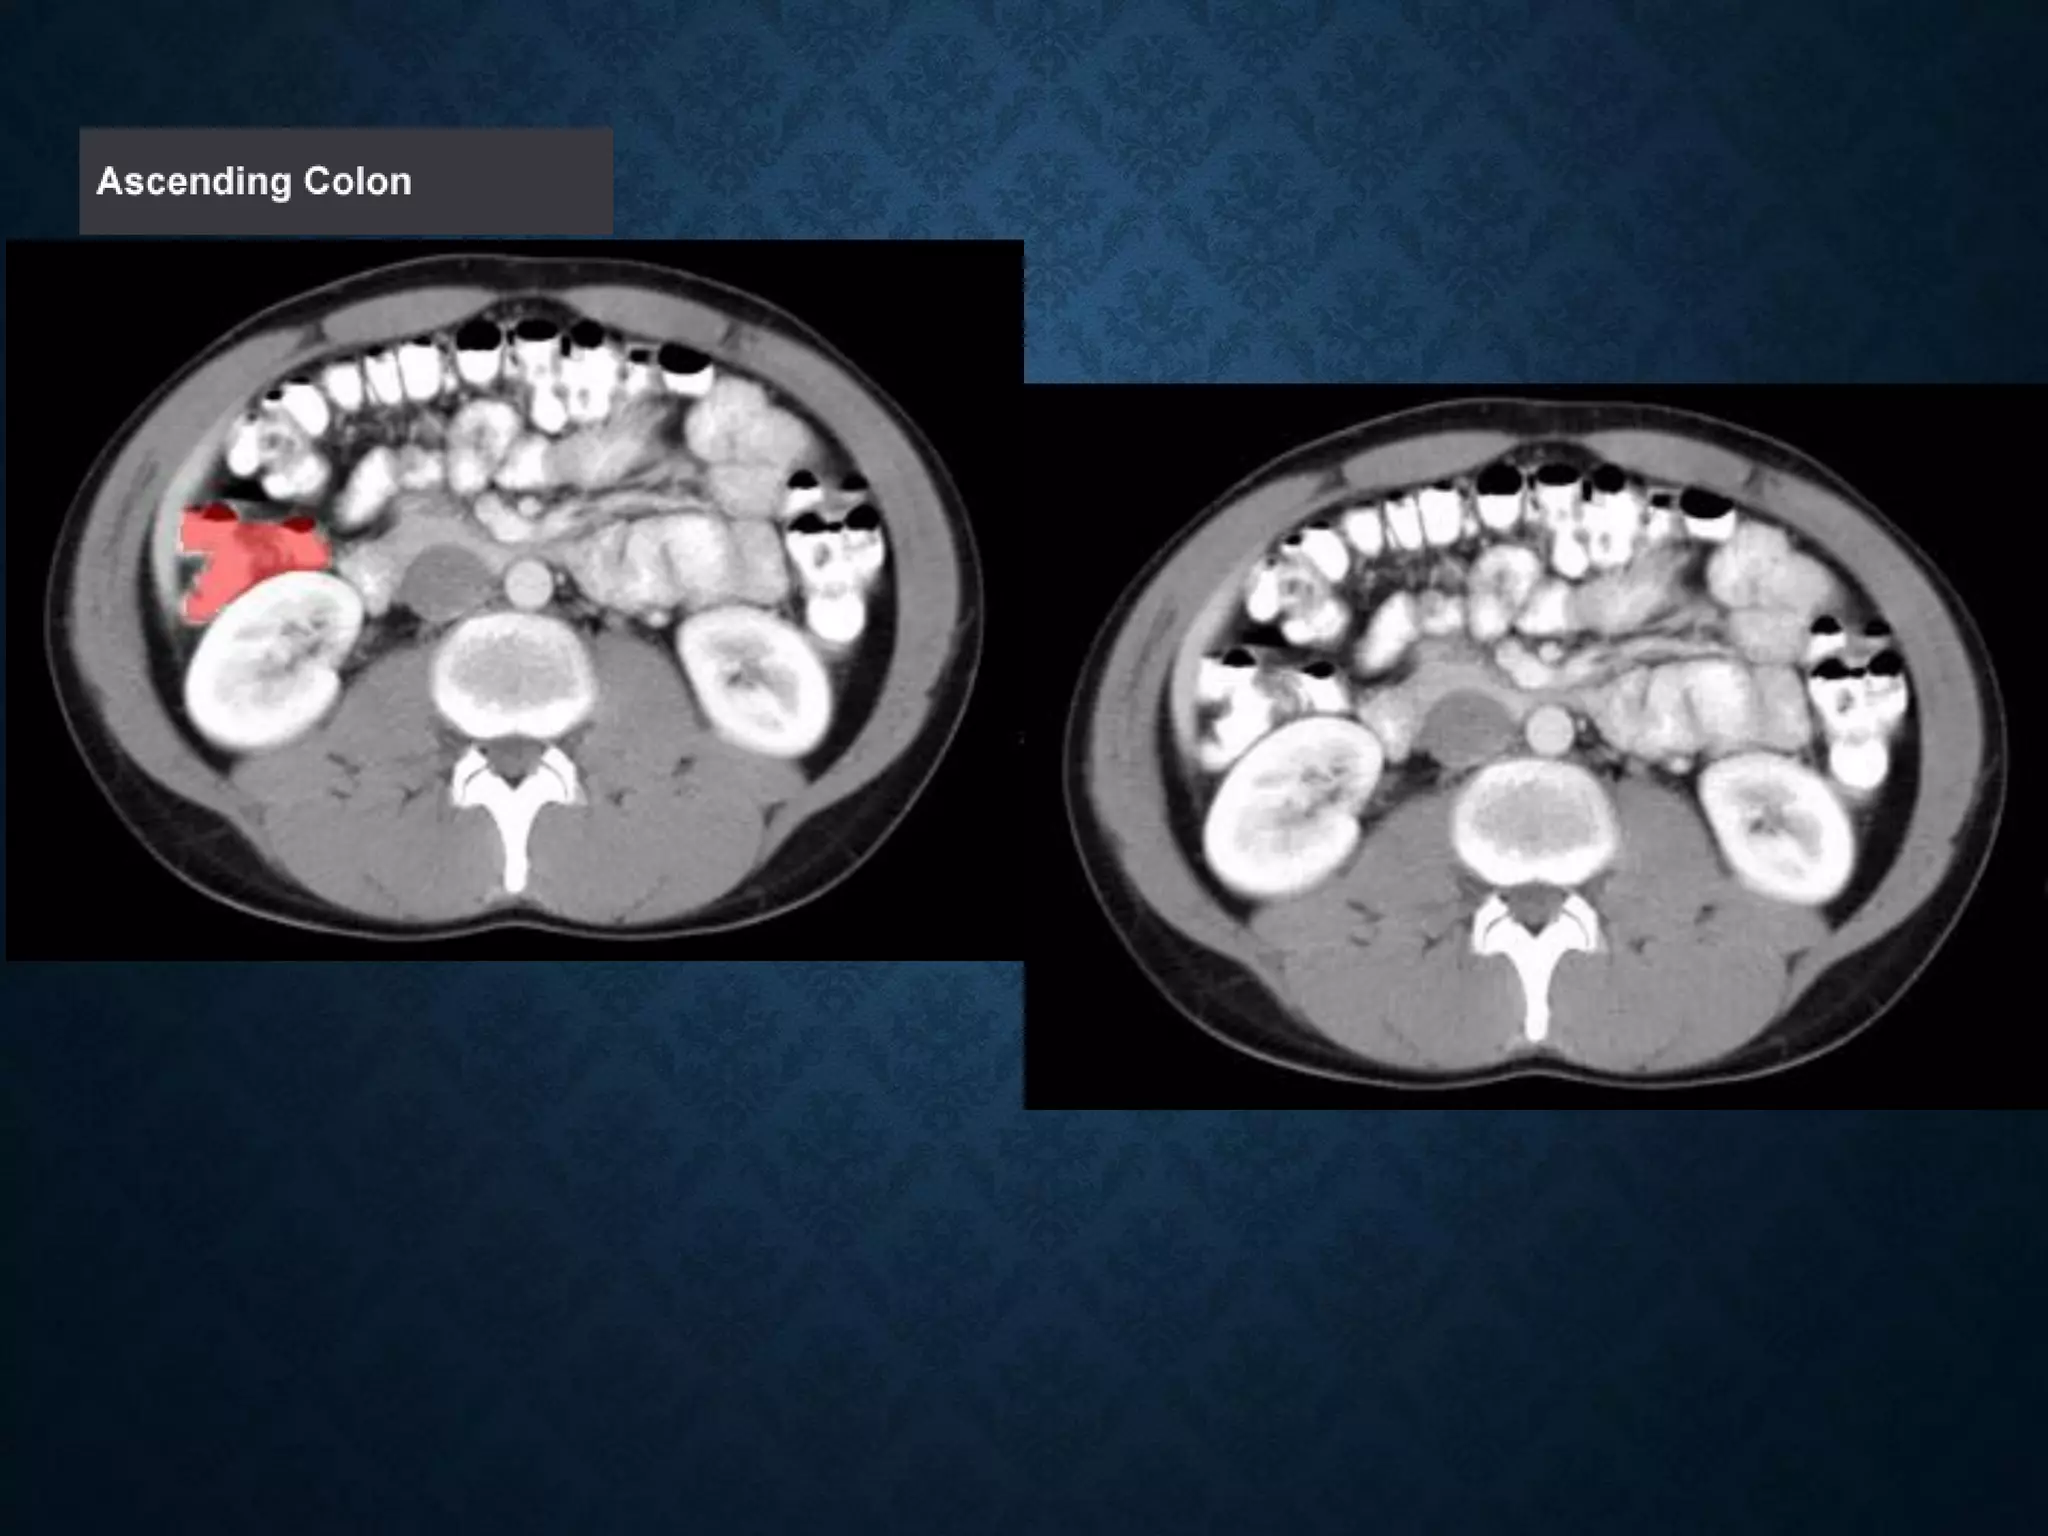

Identify the following structures in the body CT to the right. To view the location of the structure in the image click on

the label at the left and the structure will be indicated in the image. Abdominal CT scans typically begin just above

the diaphragm, so the first slice you see is of the lower chest.